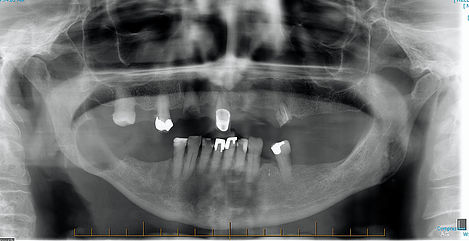

Jaw Cysts

The bone of the upper and lower jaws could develop cysts and tumors. Most jaw cysts and tumors are benign. However they still need to be removed as they will destroy the bone and teeth if they were left to grow. Generally speaking, they can require one of three treatments. Simple curettage only; simple curettage with some additional measures including long term follow up and finally resection of the bone that holds the cyst/tumor (least likely).